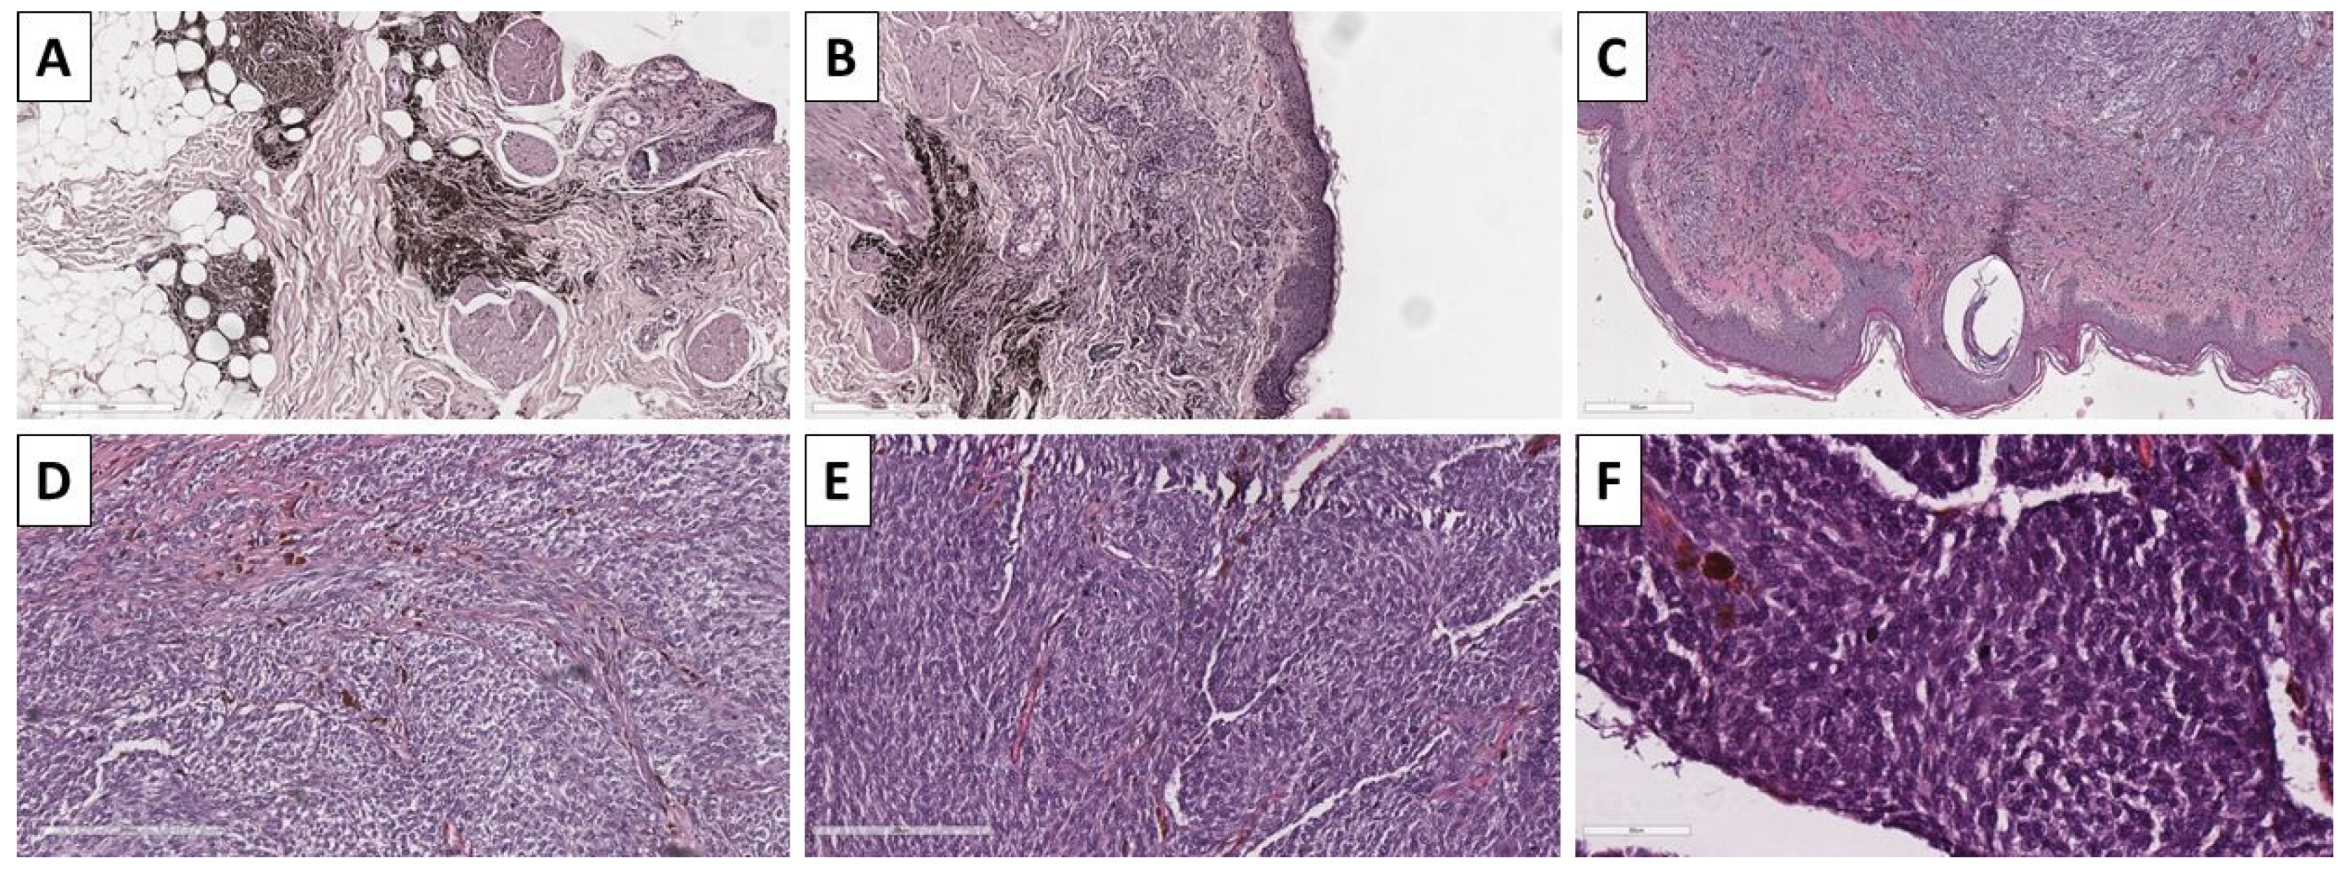

2.1. Cases 1 and 2—Conventional Dendritic Blue Nevus and Sclerotic Dendritic Blue Nevus

2.2. Case 3—Conventional Cellular Blue Nevus

2.3. Case 4—Cellular Blue Nevus as a Secondary Finding in a Patient with In Situ Clear Cell Squamous Cell Carcinoma and Superficial Spreading Melanoma

2.4. Case 5—Melanoma Arising in Blue Nevus